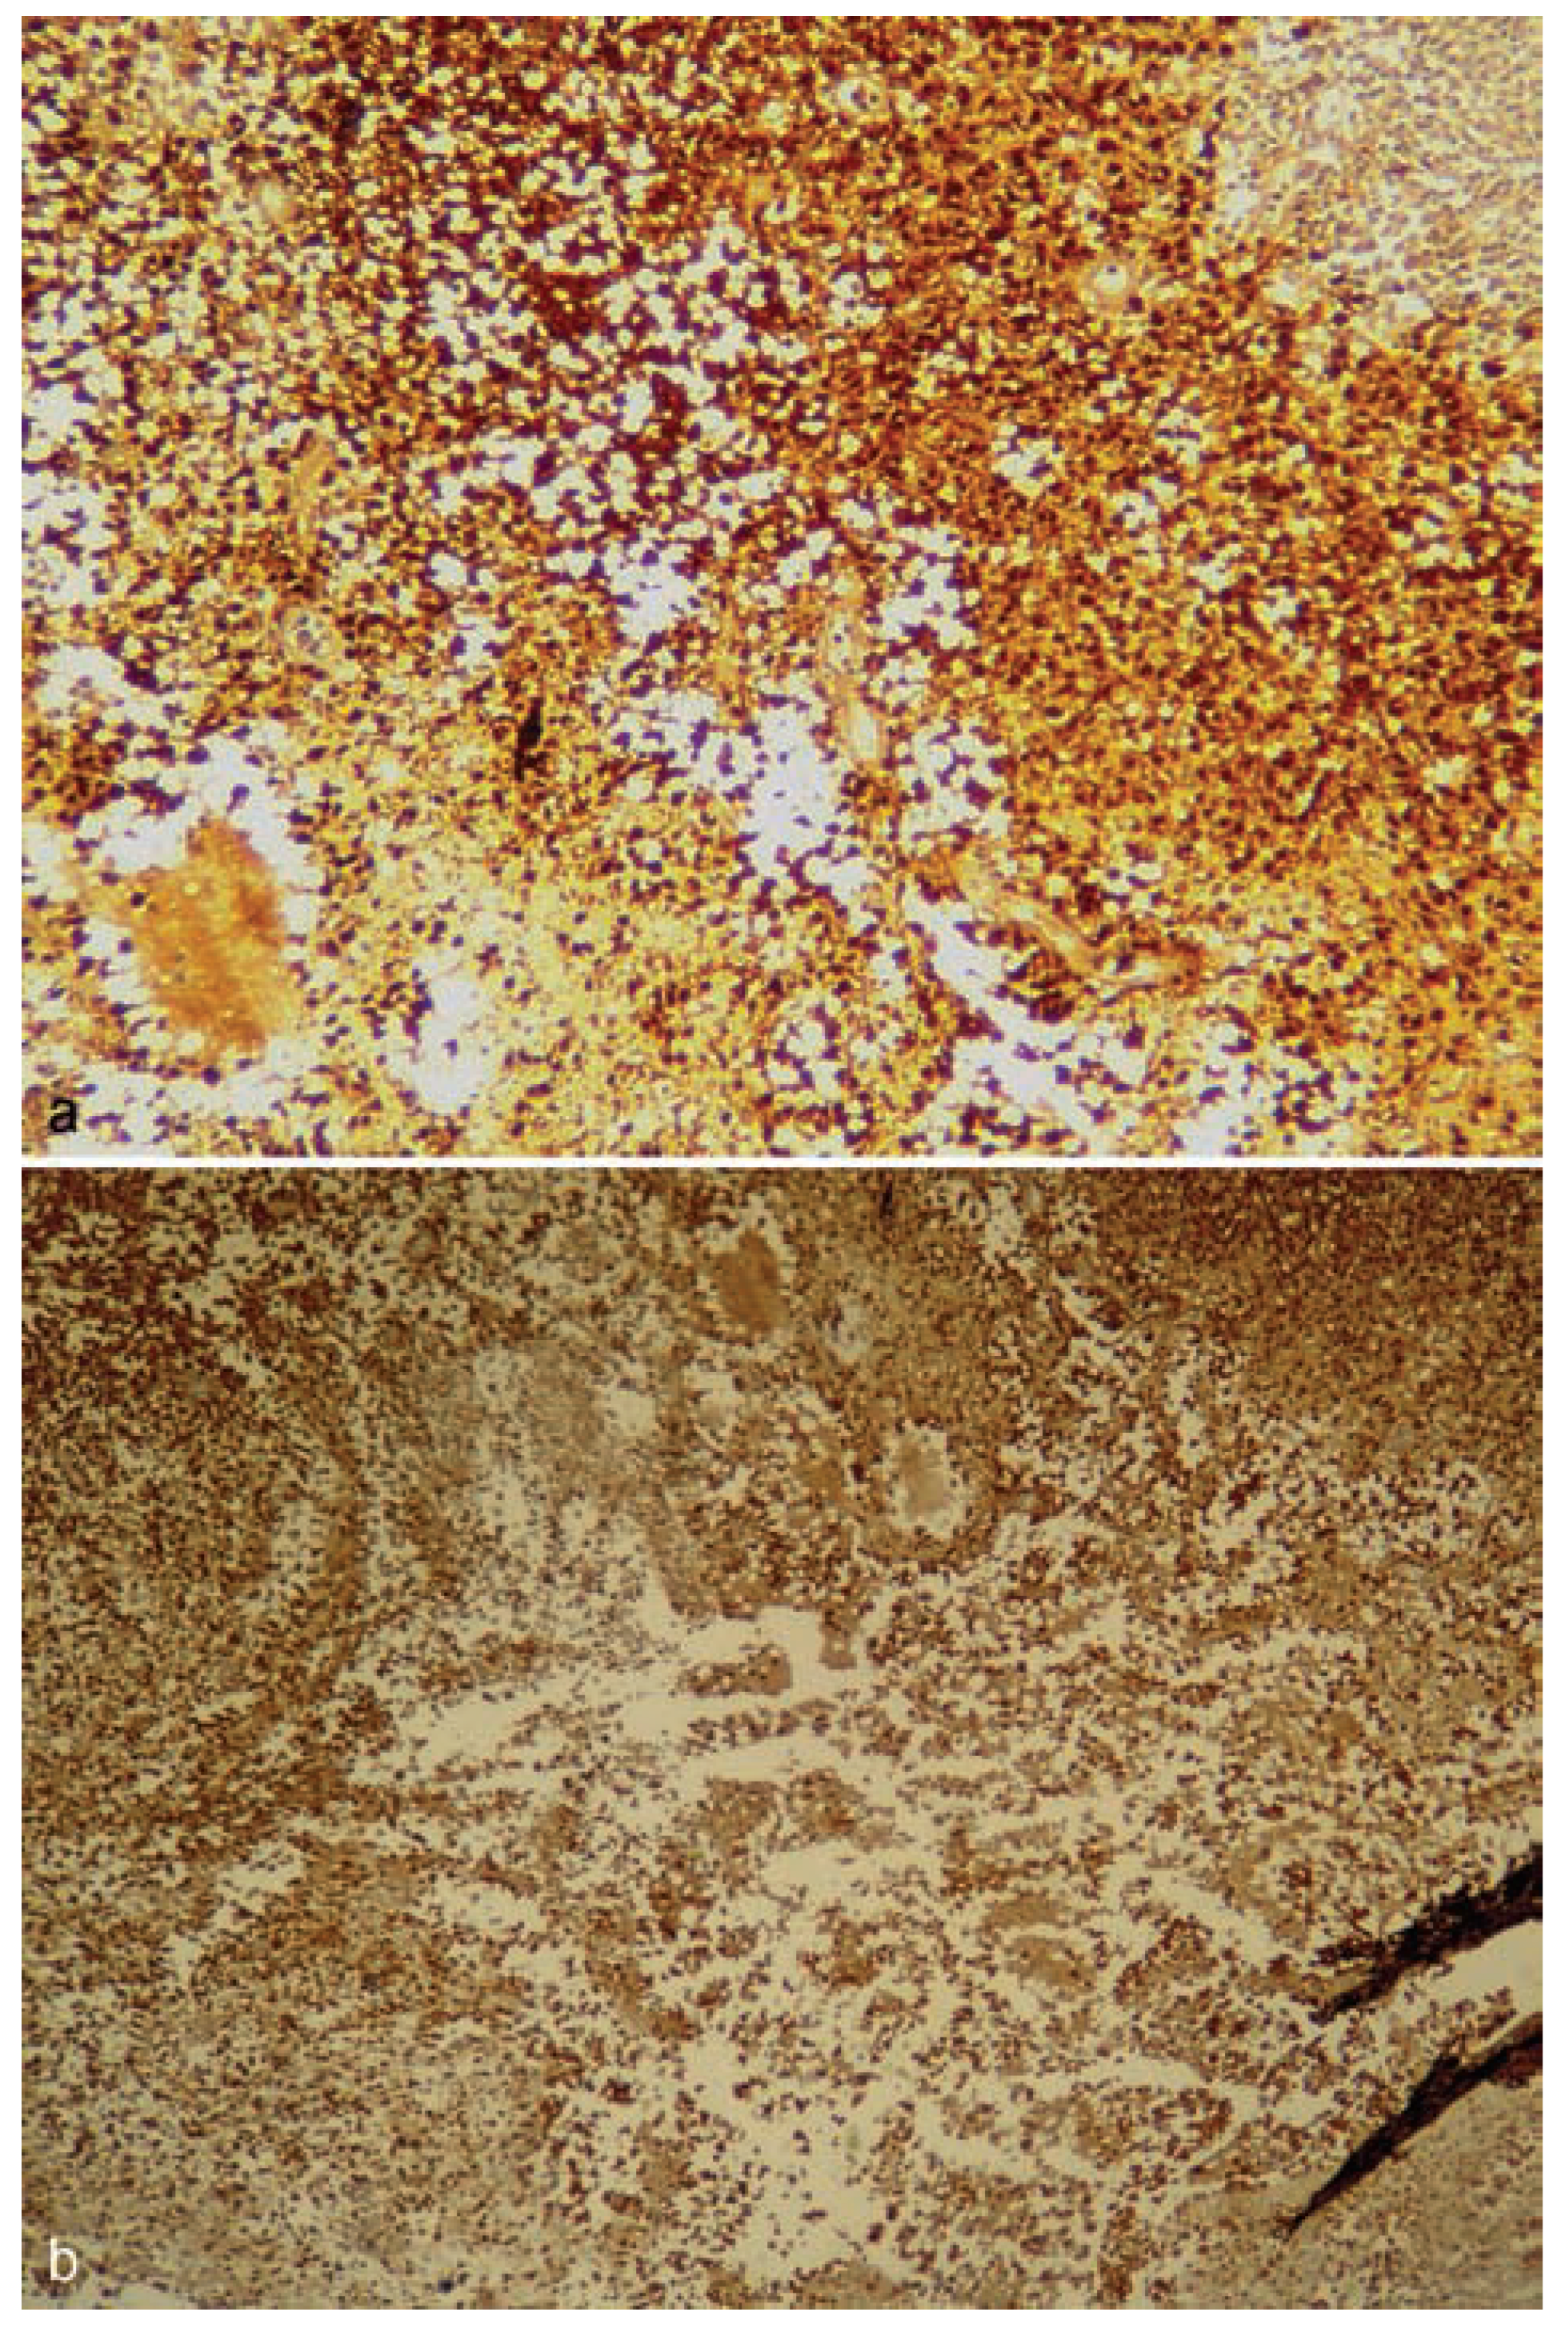

:Case Presentation